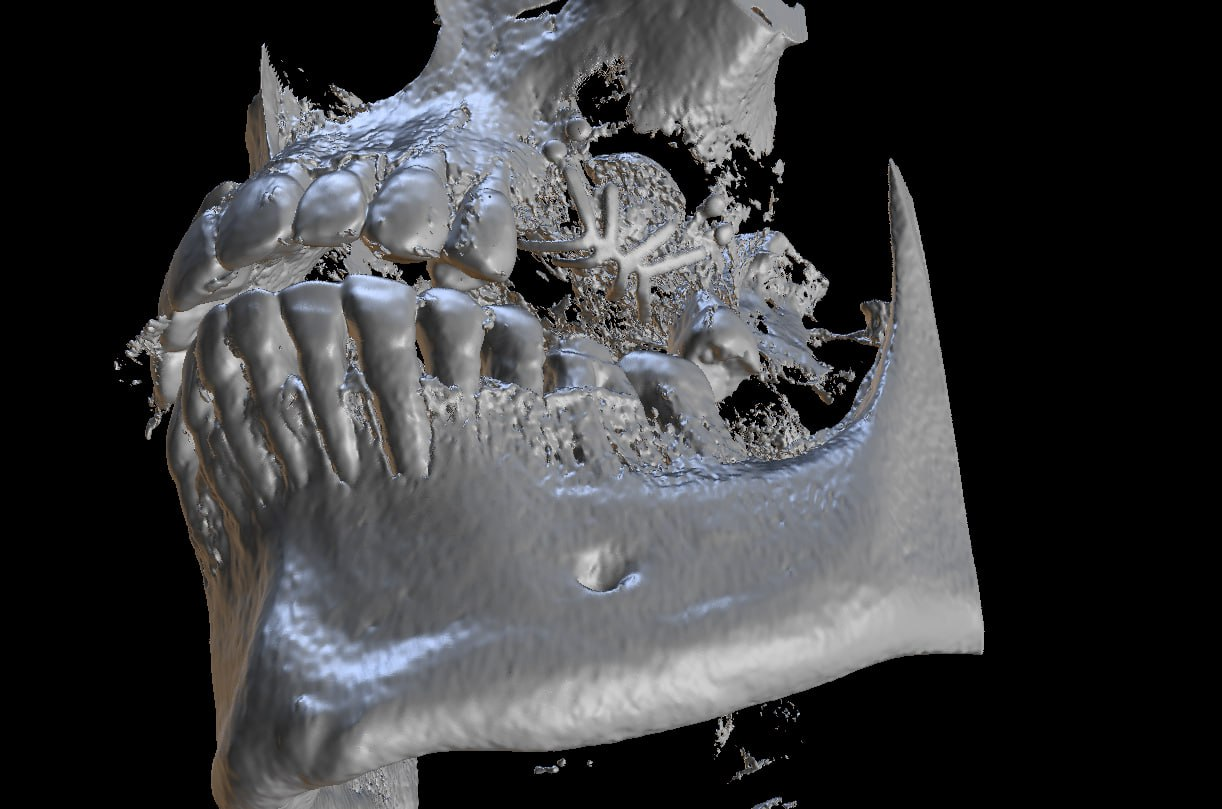

Итак, то, что вы видите, — это ортопантомограмма. Мимо пациента проехал КЛКТ-сканер (вы наверняка видели такие в клиниках, как, например, наш из клиники на «Динамо»).

Грубо говоря, каждый из серии снимков был 3D, затем софт сшил их в облако точек, и врачи получили воксельную модель челюсти пациента.

Вот красивая визуализация другого пациента, которая показывает, какого качества облако получается. Это маркетинговая картинка, на самом деле врачи никогда не делают сам рендер, а ориентируются по срезам. Тем не менее в этом инструменте можно примерять разные конструкции к пациенту и планировать установку всяких дополнительных деталей в организм, делая всё с точностью до десятой доли миллиметра:

В результате сканирования нижней части головы пациента получается некий цилиндр, в котором есть разные органы, и навигацией в этом цилиндре врачи и занимаются.